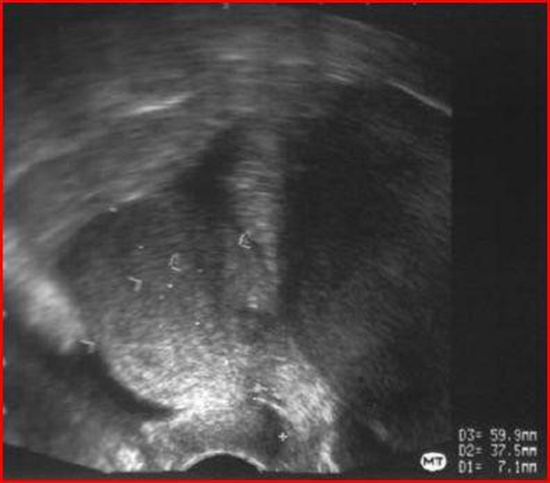

Figure 22: Trans vaginal ultrasound identifying a mass in the right ovary, measuring 71.66 mm.

Figure 23: Trans vaginal ultrasound showing a mass adherent to the uterine fundus.